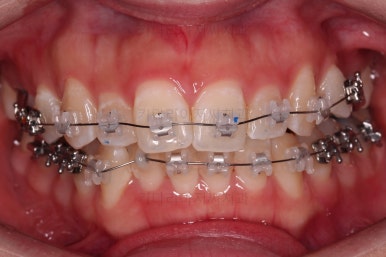

악궁확장 이후, 유지단계 동안 확장의 유지에 필요한 치아를 제외하고는 브라켓을 부착하게 됩니다.

이번 환자분이 선택한 장치는 엠파워 클리어라고 하는 자가결찰 세라믹 장치인데요.

장치 부착 직후 입이 불편해지며 입매가 약간 나오는 양상과 웃을 때 드러나는 브라켓의 느낌 참고해 주세요.

치열만 보면 매우 가지런해진 것 같죠?

이때가 대략 8개월 정도 지났을 때의 모습인데요.